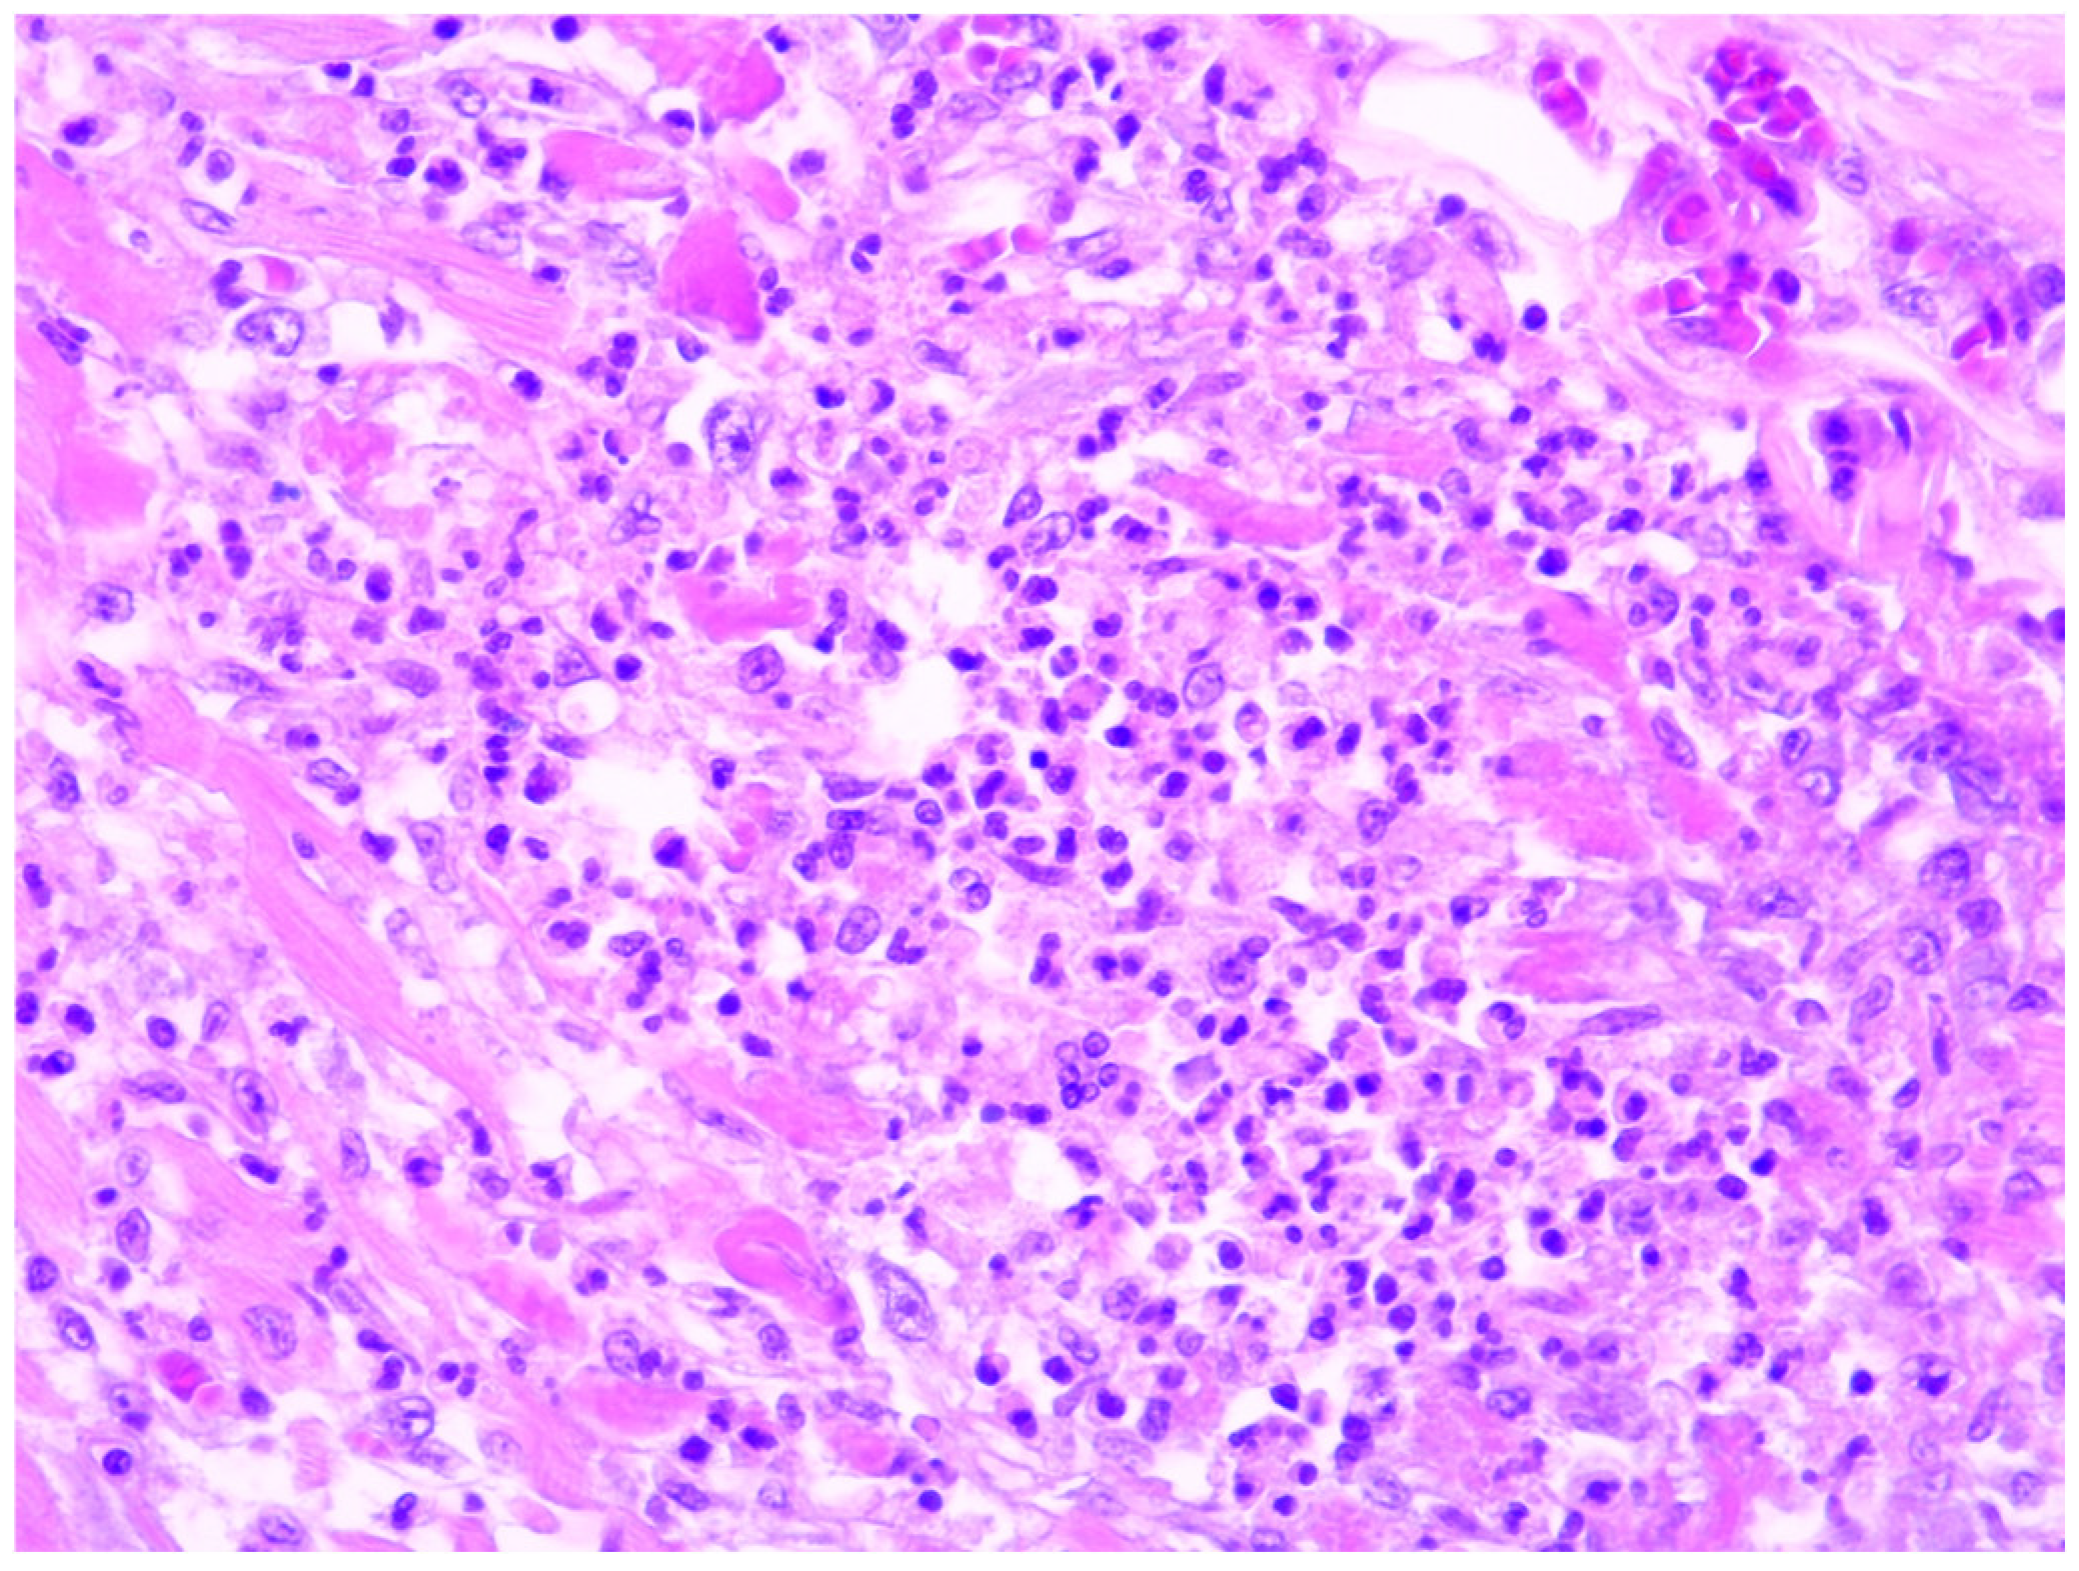

In all our cases, microscopic evaluation revealed a mixed inflammatory infiltrate dominated by neutrophils, and this was followed by macrophages, plasma cells, and a smaller number of lymphocytes (refer to Figure 1). In 17 of the cases, myocarditis was characterised by dispersed, small foci, comprising less than 15% of the entire section and corresponding to grade 2 inflammation severity. Notably, no specific changes in the myocardium were observed during the gross examination at the autopsy. The inflammation was more pronounced in only five cases, occupying between 20 to 40% of a section. In these particular cases, the forensic doctor noticed dark-coloured areas, changes in consistency, or yellowish dots while examining the myocardial sections macroscopically (Figure 2). However, these findings did not raise suspicion of myocarditis at that time.

Figure 1. A sample of acute myocarditis focus composed of neutrophils, macrophages, and a few plasma cells (HE, 400×).